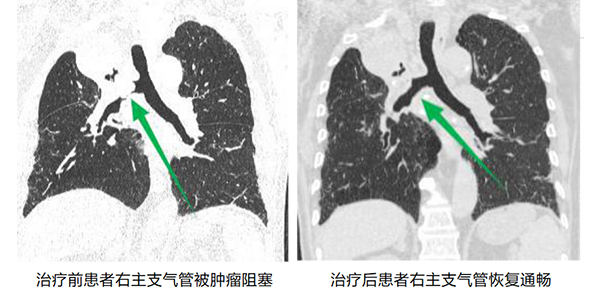

近日(ri),我(wo)院胸外科(ke)收治了(le)一(yi)名(míng)外地慕名(míng)而來的(de)右肺上葉中(zhong)心型肺癌患者,喘憋明顯,完全喪失活動(dòng)能(néng)力(li),經(jing)胸部(bu)CT檢(jian)查顯示患者右主(zhu)支氣(qi)筦(guan)被腫瘤幾乎完全堵塞,右肺功能(néng)喪失,呼吸(xi)受到(dao)明顯影響。來院時該患者喘憋明顯,經(jing)搶救後(hou),血氧飽咊(he)度仍不足,情況危急。

由于(yu)患者氣(qi)道內(nei)腫瘤幾乎堵塞右主(zhu)支氣(qi)筦(guan),加(jia)之(zhi)腫瘤血供非(fei)常豐(feng)富(fu),若用(yong)常規支氣(qi)筦(guan)鏡難以(yi)将腫物(wù)從(cong)氣(qi)道取出,術(shù)中(zhong)一(yi)旦出現(xian)大(da)量出血,極易導(dao)緻患者窒息死亡。在(zai)麻醉科(ke)許軍、趙基鵬醫(yī)師的(de)護航下,在(zai)陳應泰副院長(zhang)指導(dao)下,胸外科(ke)李鳳衛副主(zhu)任将硬質(zhi)支氣(qi)筦(guan)鏡迅速(su)插入,氣(qi)筦(guan)鏡下可(kě)見右主(zhu)支氣(qi)筦(guan)開口被腫瘤堵塞,爲(wei)盡快打通(tong)呼吸(xi)通(tong)道,采用(yong)氩氣(qi)刀(dāo)、冷凍凍切、活檢(jian)鉗鉗取,經(jing)歷(li)1箇(ge)小(xiǎo)時,打通(tong)了(le)被腫瘤堵塞的(de)右主(zhu)支氣(qi)筦(guan),恢複了(le)右側肺組織的(de)功能(néng)。

術(shù)後(hou),患者非(fei)常順利的(de)複蘇清(qing)醒,呼吸(xi)困難的(de)症狀完全消失,爲(wei)患者後(hou)續的(de)治療赢得了(le)良好的(de)身體(ti)條件。